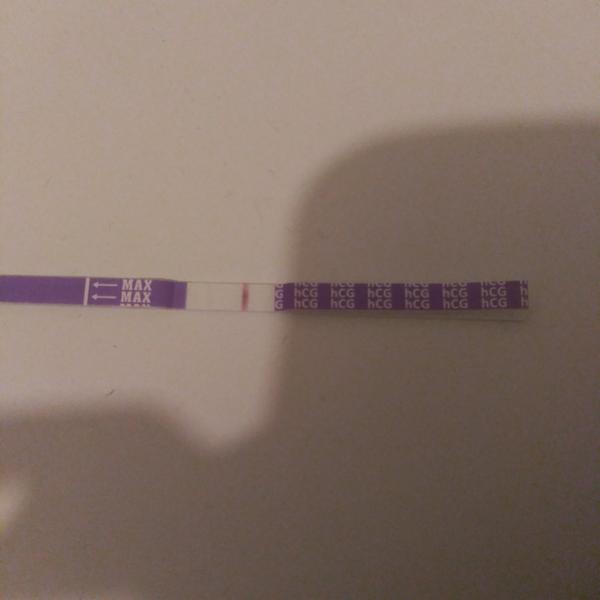

bola som u svojho gynekológa a spravil mi ultrazvuk. Vraj si nie je istý, či som tehotná, alebo mám zrazeninu. V krvi mám negatívny výsledok, ale test mi stále ukazuje pozitívny výsledok. Testy sú robené od 22.10 každý tretí deň.

Posledný piaty test bol robený 2.11.2019.